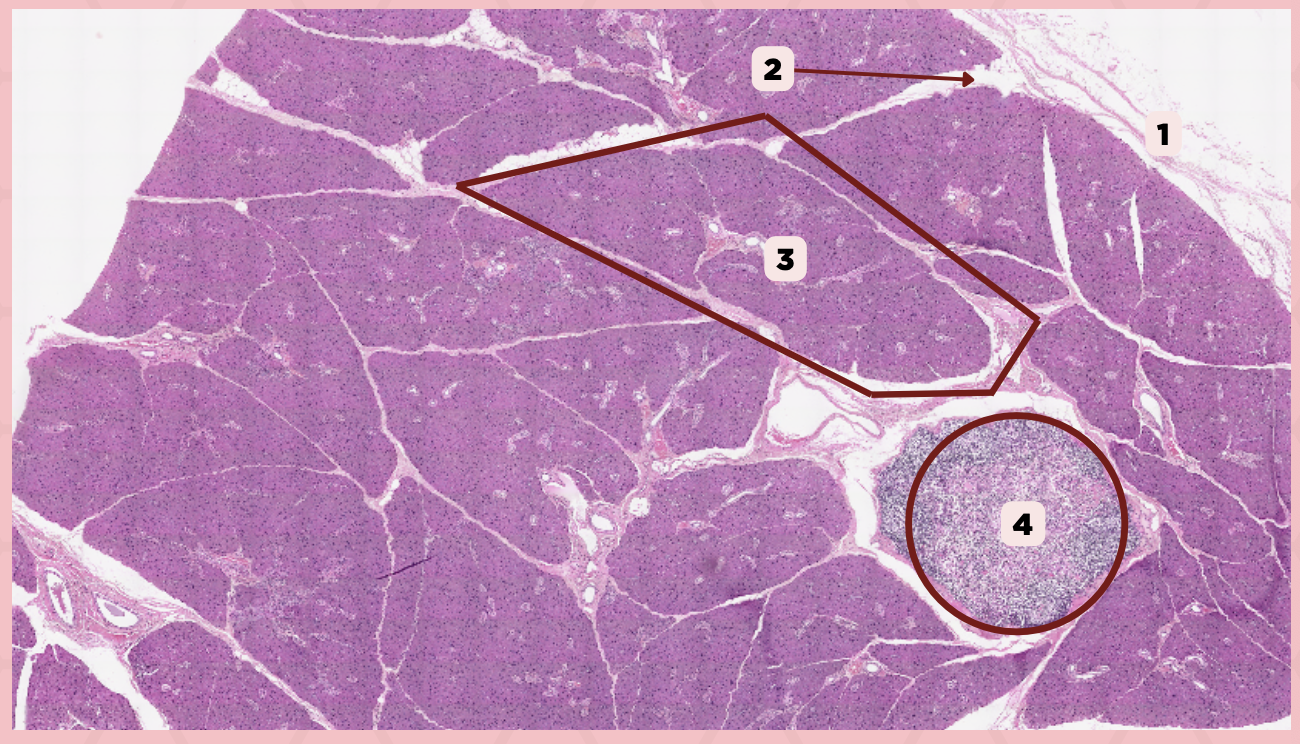

Parotid

Identify the specimen.

Capsule

Identify the structure labeled as 1.

Septa

Identify the structure labeled as 2.

Lobule

Identify the structure labeled as 3.

Lymph Node

Identify the structure labeled as 4.

C) Septa

Which of the following structures shown delineate the lobes and lobules of the parotid gland?

A) Capsule

B) Lobule

C) Septa

D) Lymph Nodes

A) Capsule

Which of the following structures encapsulates the parotid gland?

A) Capsule

B) Lobule

C) Septa

D) Lymph Nodes